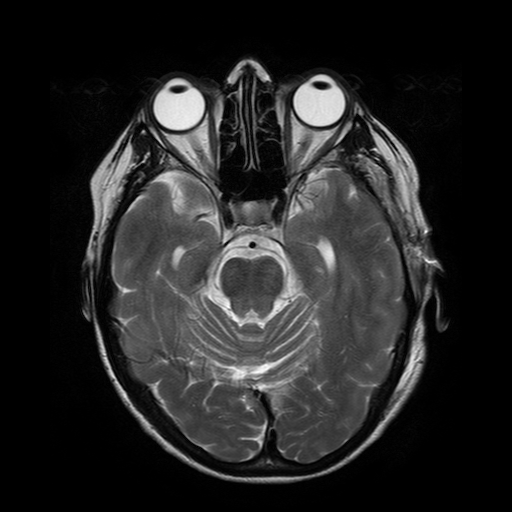

To simulate various input noise levels, several values for have been selected in the range . The set of high-quality magnitude MR test images used is shown in Fig. 6, and may be obtained from http://bigwww.epfl.ch/luisier/MRIdenoising/TestImages.zip.

V-C Denoising of a magnitude MR knee image

We have also applied our CURE-LET denoising algorithms to an actual magnitude MR image of the knee. This 16-bit raw image has been acquired on a Siemens 1.5 Tesla Magnetom Sonata MR system, following a sagittal T2-weighted protocol. The standard deviation of the complex Gaussian noise has been estimated from a signal-free region of the squared data, as , and subsequently treated as known.

Fig. 11 shows the denoising results of the various CURE-LET algorithms. As observed, the noise is efficiently attenuated and the contrast is significantly improved, owing to a proper reduction of the signal-dependent bias introduced by the noise.